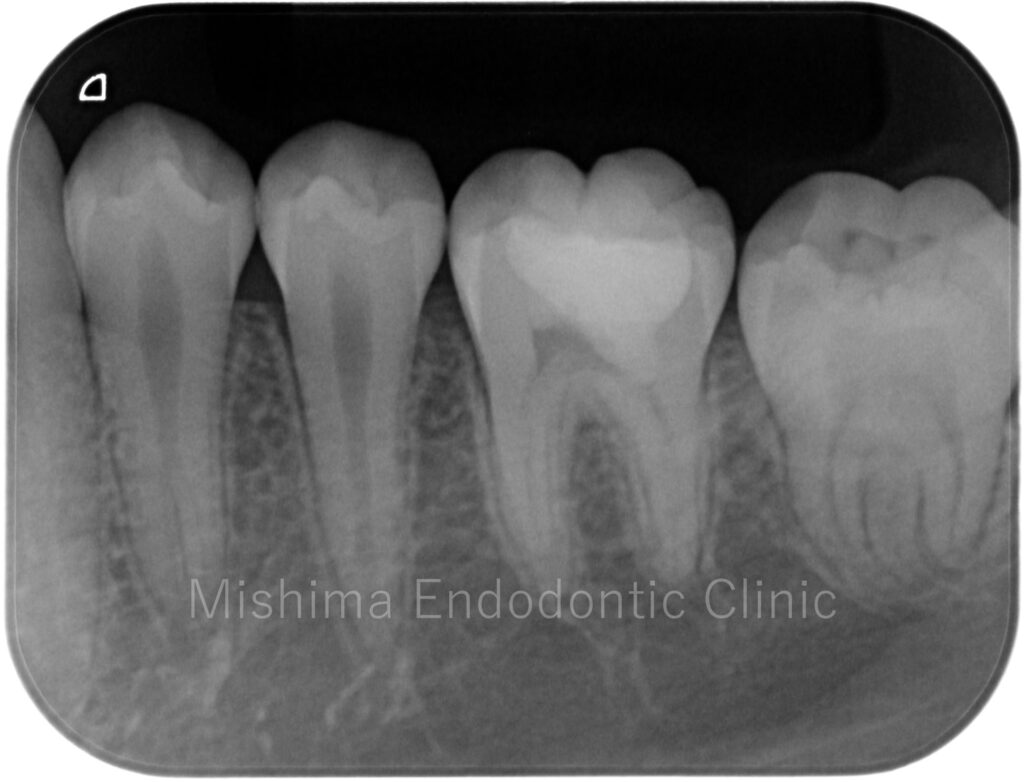

After

| 治療内容 | 咬合面にCRにて修復されており、CR下にてカリエスを認めた。歯髄診査にて歯髄は正常歯髄と診断。カリエスを除去していくと露髄を認め、壊死歯髄を除去、部分断髄し、バイオデンティンにて覆髄、CRにて最終修復まで行った。 |

術直後